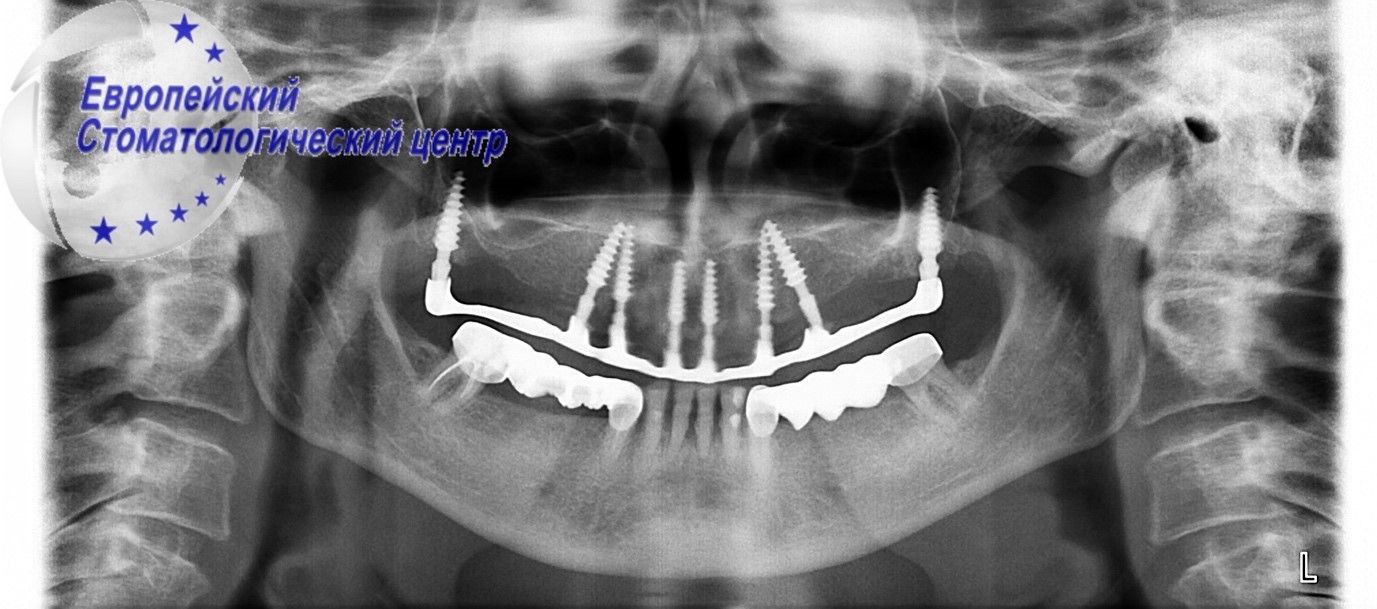

Diagnosed with progressive generalized periodontitis. It was decided to remove all existing teeth with immediate implantation. The operation to install implants was also complicated by the presence of infected tissues in the oral cavity. After tooth extraction, laser disinfection and curettage of the extracted teeth were performed. Doctors of the European Dental Center managed to remove damaged teeth in the upper and lower jaw in one surgical procedure, install 17 implants without additional incisions and complications, and establish temporary non-removable orthopedic structures in a day (see pic. 3-4).

Picture 3

Picture 4

Currently, the patient expects full integration of implants and the installation of permanent fixed structures. Fast (in 3 days) patient rehabilitation is achieved thanks to many years of experience, continuous improvement, and the availability of modern dental equipment at the European Dental Center.